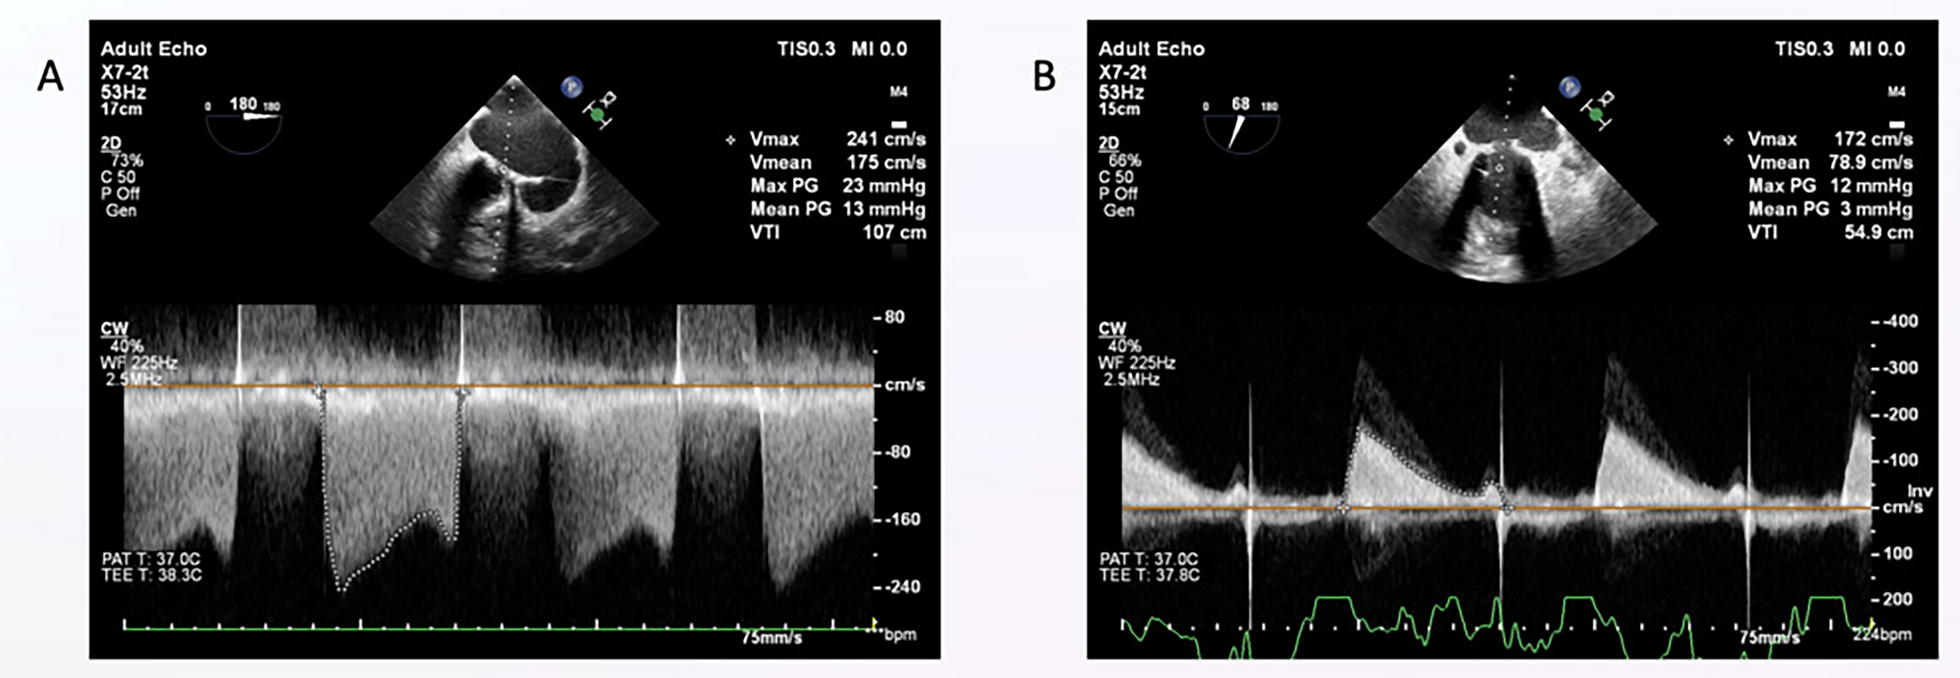

Our results are consistent with those of Reddy et al. [5], who performed strain imaging to evaluate the early effects of PBMV on the mechanics of the left atrium for 29 patients with MS. They compared the results with those of 30 age- and sex-matched healthy control subjects. The MS cases showed a significant increase in the mean left atrial diameter and left atrial area compared to the control group. Also, the MS cases had significantly lower left atrial strain at baseline compared to the control group. Similar to our results, they observed that patients with severe MS exhibited impaired LA GLS, which improved within 24–48 h after BMV (p < 0.001). Furthermore, they found a significant decrease in the mean mitral gradient (MMG) and sPAP (both p < 0.001) and A significant rise IN MVA (p < 0.001) after BMV.

In the present study, a significant positive correlation was found between immediate LA GLS and the achieved MVA (0.64, p < 0.01), and the function class was improved significantly after valvuloplasty (p < 0.01). This correlation was unique to our study and reflected the efficiency and success of BVM in enhancing both the left atrial volume and function. Ahmed [15] found a significant positive correlation between the left atrial longitudinal strain improvement and drop in the mean trans-mitral pressure gradient, as well as left atrial volume reductions at 12 months after BMV. Rohani et al. [14] reported a significant correlation between the drop in mean transmitral pressure gradient and left atrial global longitudinal strain (r = 0.60, p < 0.01) after PTMC. However, a non-significant correlation was observed between the PALS and the MVA (r = 0.03). Many studies have also demonstrated the improvement of function class after a successful BMV [6, 13, 15].